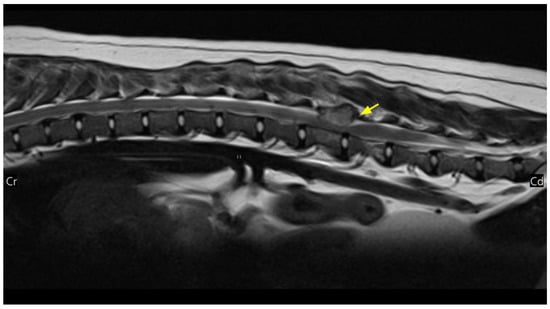

2. Case Description